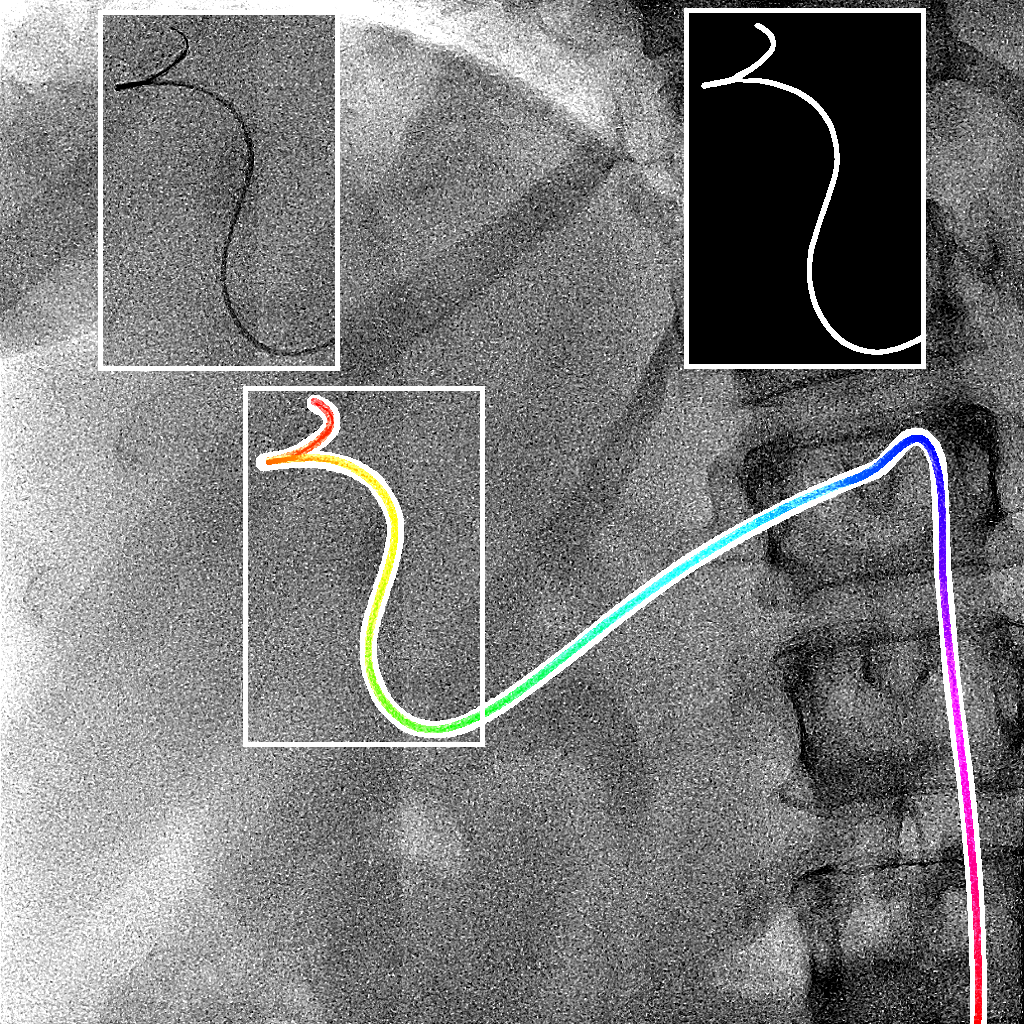

The output of the neural network is first thresholded with a threshold (between 0 and 1) and then skeletonized [19]. Next, the branches (ordered sets of pixels) are determined based on connectivity. Connection points are created between close branches. If the closest points between two branches are within a distance pixels, we consider this to be a possible connection, and there can be only one connection between two particular branches. Then, to link the branches, three steps are done (Fig. 2). First, for each connection, we divide and merge branches in order to have the longest branches. Second, loops are detected and merged following the direction at the crossing point. We have a loop in a branch when two points, within a distance pixels, have their distance along the branch of at least pixels. Before the third step, the first and second steps are repeated a second time with a distance superior to . Finally, in the last step, the remaining connected branches larger than pixels are considered as incomplete loops or straight loops due to foreshortening. We process them similarly as the second step by closing the two endpoints of their branch. When all the potential links have been processed, we keep the longest connected set of branches and choose amongst the two endpoints the farthest from the image border as the tip of the catheter centerline. Finally, the centerline is smoothed by fitting a spline.

We evaluate using the tip distance error (i.e. the distance between the annotated catheter tip and the tip of the segmented catheter), and the average distance between the manually segmented catheter and the automatically segmented catheter. Figure 3 shows the tip and catheter distances results. We compute the precision of the tip between consecutive frames. The median, average, minimum and maximum of the standard deviation per sequence of the tip distance error are respectively 0.7 mm, 4.9 mm, 0.1 mm and 55.7 mm. Five examples of segmentation are shown in Figure 4. In the third frame, the segmentation is going too far and follows part of the vertebrae. The fourth frame misses the proximal part of the catheter. The last frame is the only sequence with significant false positives. It is less noisy because it has been acquired with higher radiation dose. The neural network was not trained for such sequence.